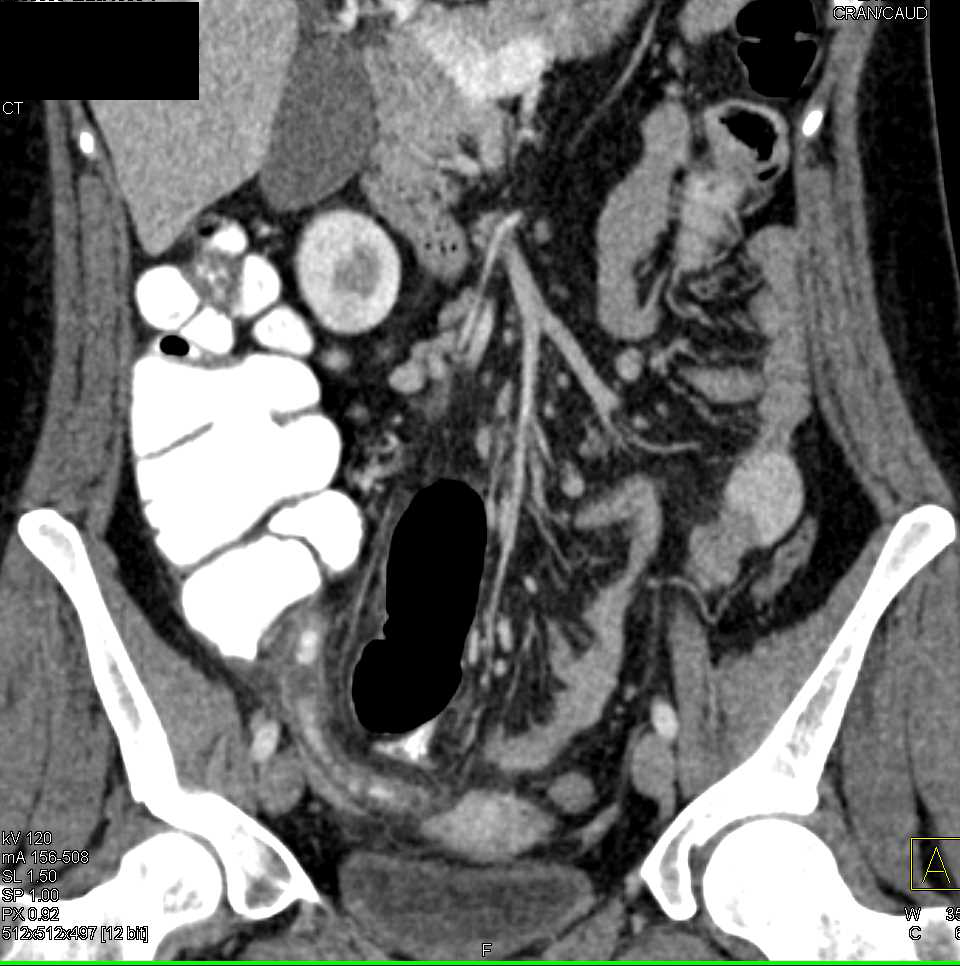

Incidental Small Bowel Lipoma (Jejunum) in Patient with MCN (Mucinous Cystic Neoplasm) Pancreas